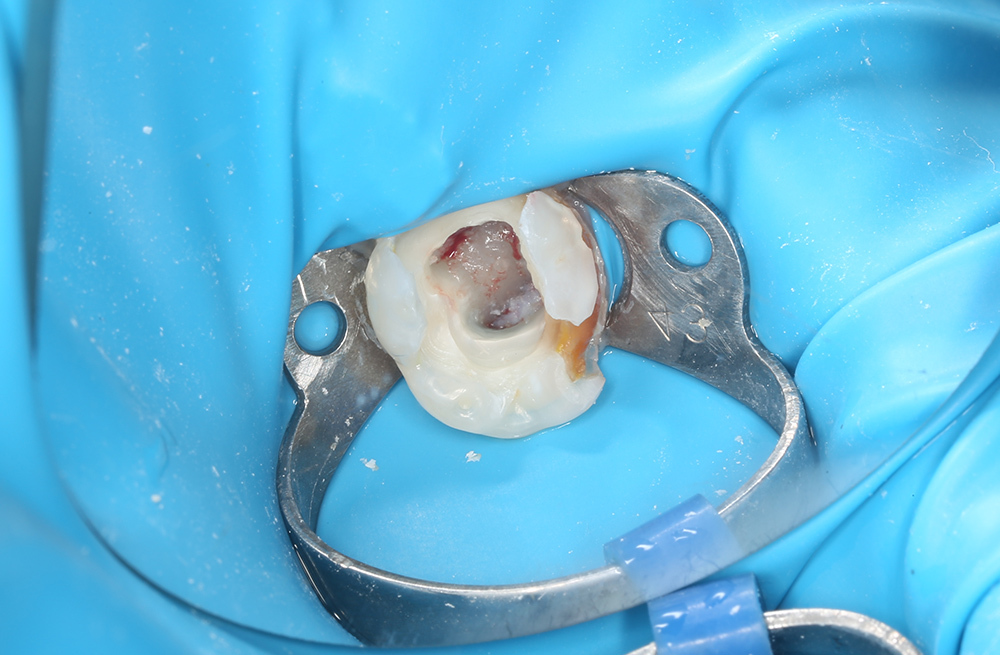

Сохранение зуба при обратимом пульпите